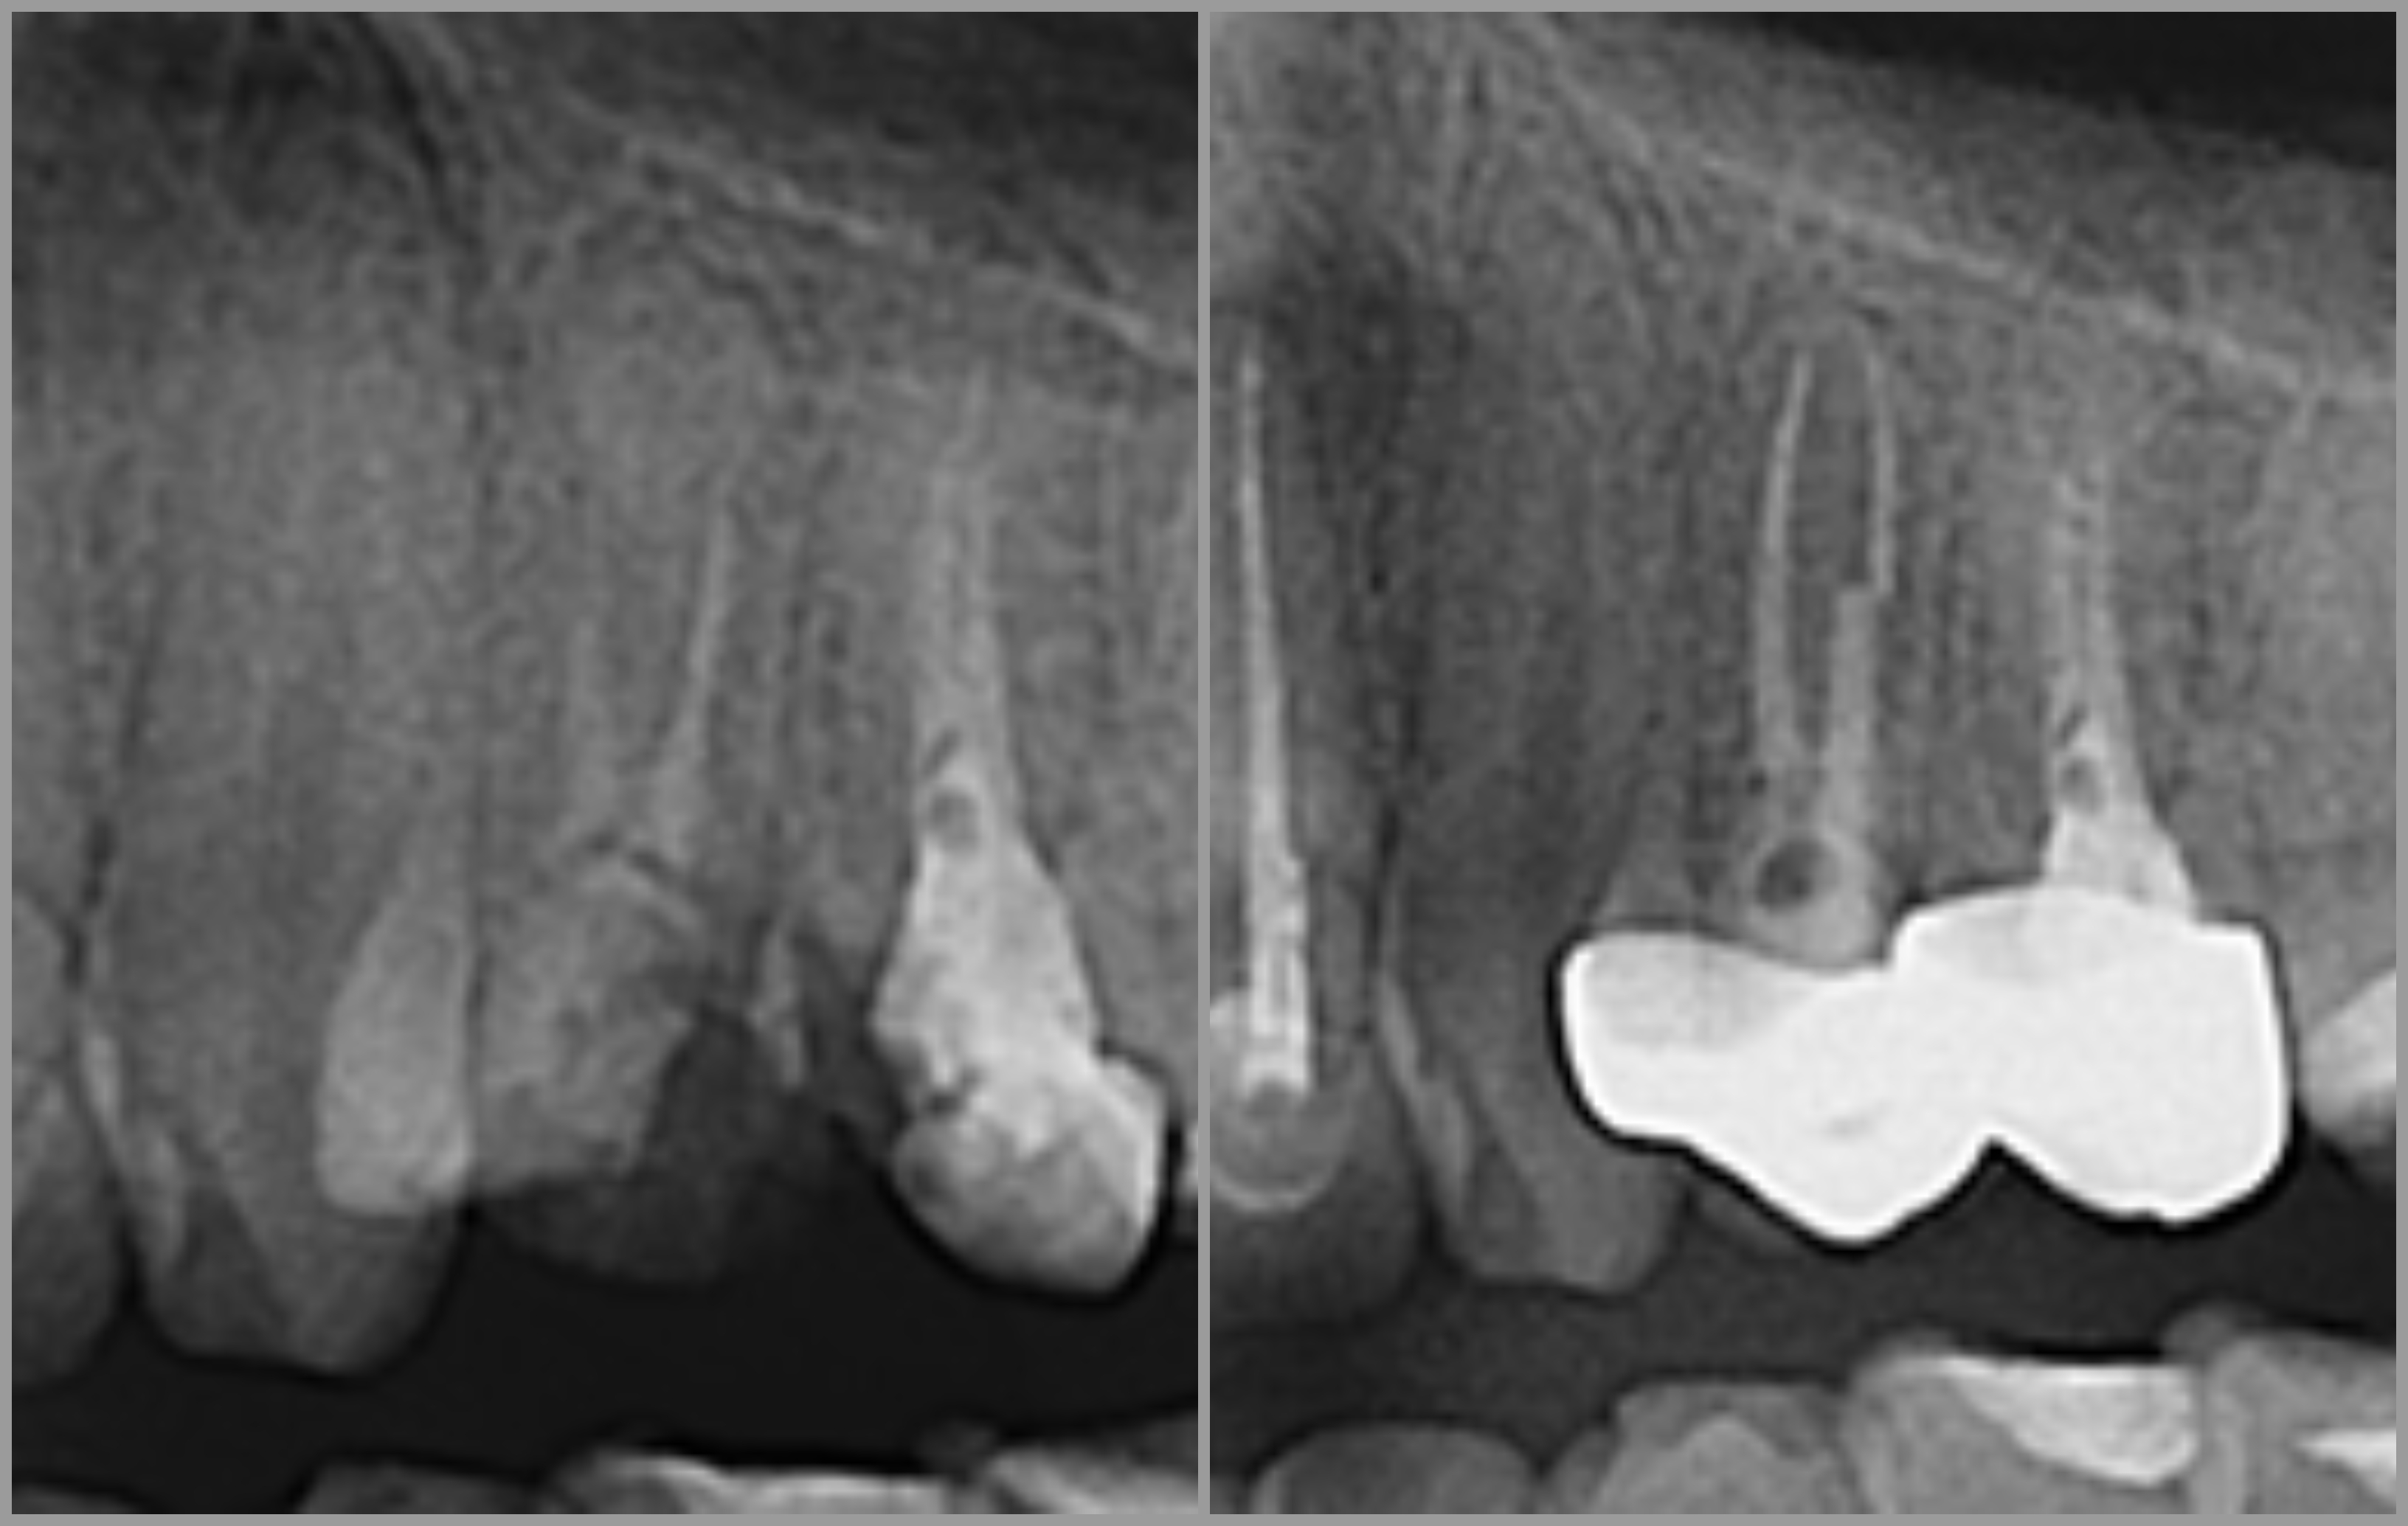

Ako se zub s upalnim procesom ne liječi, dolazi do širenja upale na kost i stvaranja upalnog procesa oko vrha korijena, odnosno dolazi do razvoja granuloma.

Endodontska terapija započinje uklanjanjem karijesom zahvaćenog zubnog tkiva, nakon čega se odstranjuje upaljena zubna pulpa te se kemijski i mehanički čisti zubni kanal radi uklanjanja bakterija i inficiranog dentina.

Tretirani zub jednako je funkcionalan kao i vitalni zubi, a sam korijen se može koristiti za protetske nadomjestke (krunice i mostove).

Reciproc predstavlja potpuno novi koncept u liječenju korijenskih kanala zuba. Postupak u kojem se primjenjuje ovaj sustav potpuno je siguran, brz, jednostavan i bezbolan. U većini slučajeva za liječenje zuba dovoljan je jedan posjet ordinaciji.